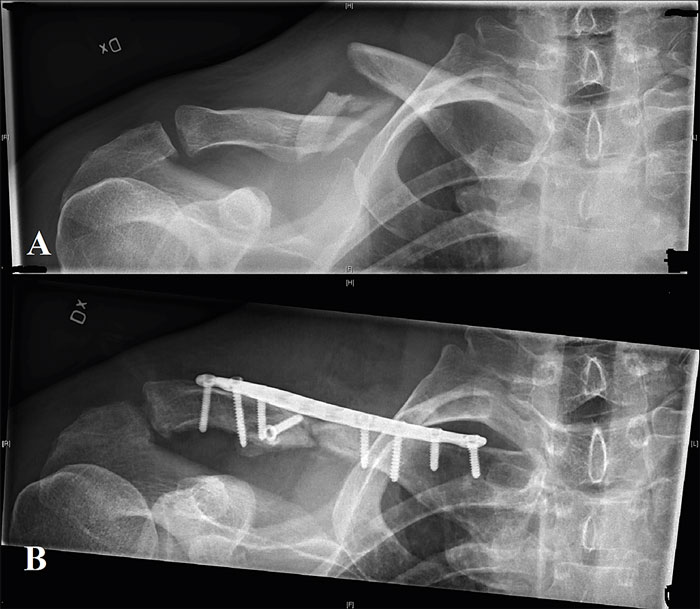

Anteroposterior projektion som visar fixation av dislokerad diafysär klavikelfraktur typ 2B2 (A) med lågprofilerad vinkelstabil platta och skruvar (B).